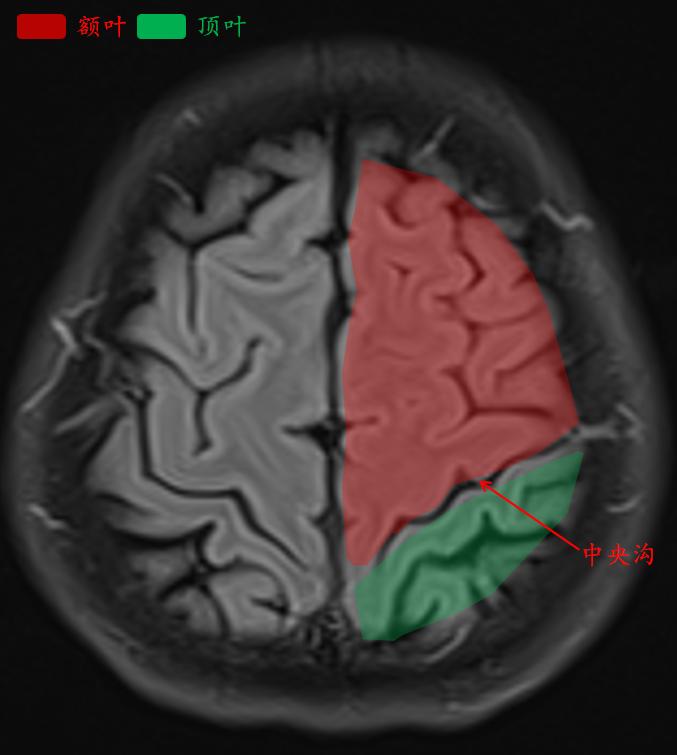

这就是常规医院扫描的t2-flair的相似层厚层间距的图像。

中央沟是额叶和顶叶的分界线。